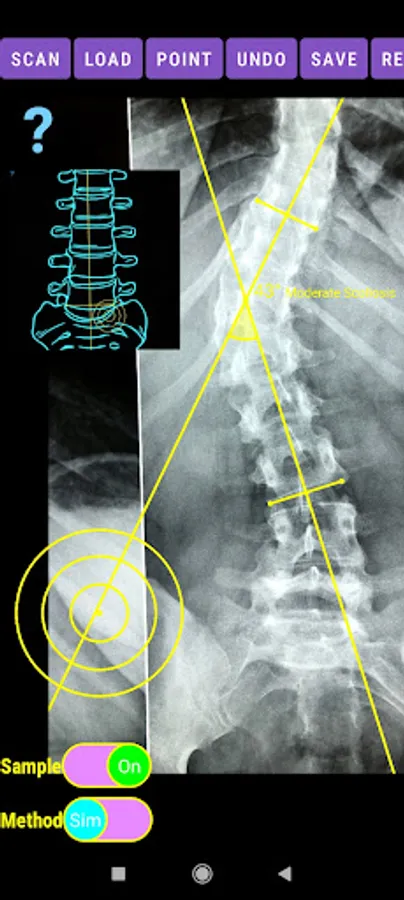

-Offers a very convenient way to determine the most accurate possibly way at once. By marking four points at the same X-ray, at each spine the App calculates the Cobb angle. In cases where values are out of normal ranges, the scoliosis is categorized according to measured angle as mild, moderate, severe. To simplify the process and to minimize inter-observer errors usually by not selecting the actual end vertebra, the app offers also in ext mode the ability to draw the vertical reference line through the patient’s sacrum and to identify more easily the end vertebrae (ext method).

The app offers a very convenient way to asses spinal deformity by measuring the Cobb angle. The first thing is to load one image from your photo library or capture a photo from x-rays photos of a patient. The app offers two measuring methods, the simple (Sim.) and the extended (Ext.). By clicking the relevant option, the option is highlighted and the respective method is activated.